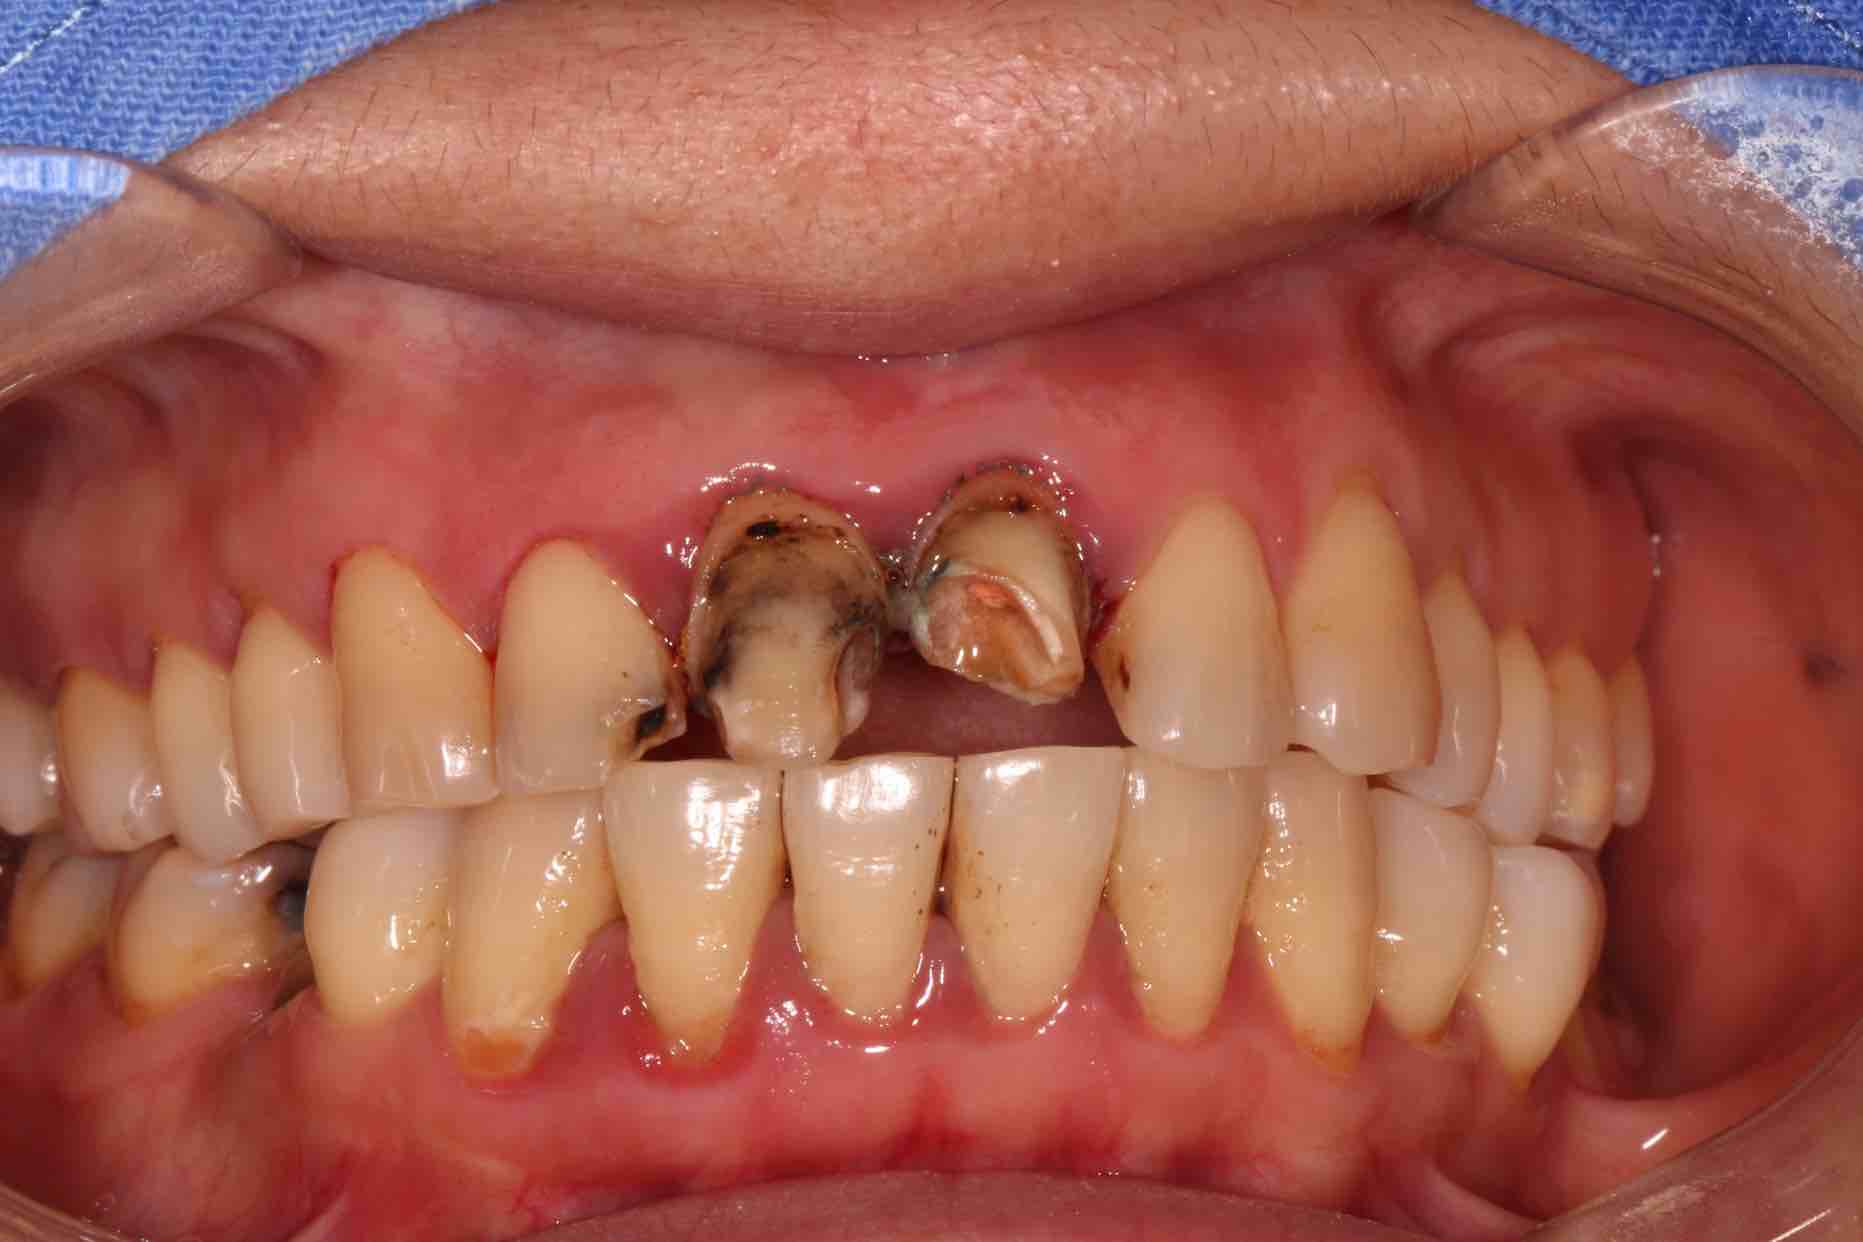

患者中年女性,11、21外院制作烤瓷冠,冠边缘不密合,牙龈退缩发黑,龈缘红肿,颜色不美观且X线检查21根管治疗不完善,由于牙冠不密合,11严重龋坏已有牙髓炎症状,我们对11进行了根管治疗,21进行了根管再治疗,最后CEREC扫描修复。